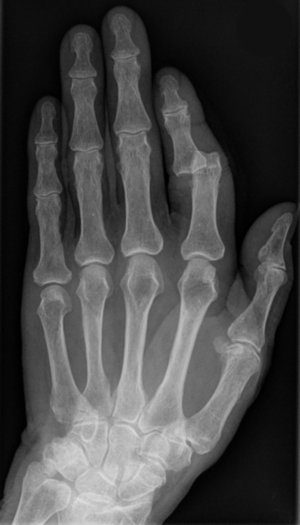

Ausgerenkter Zeigefinger - Hellerhoff commons.wikimedia.org, CC BY-SA 3.0

Bei den meisten Verletzungen im Sport sind: Haut, Muskulatur, Sehnen, Bänder, Knochen oder der Kopf betroffen.